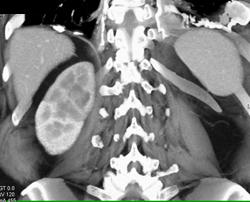

Transitional Cell Carcinoma